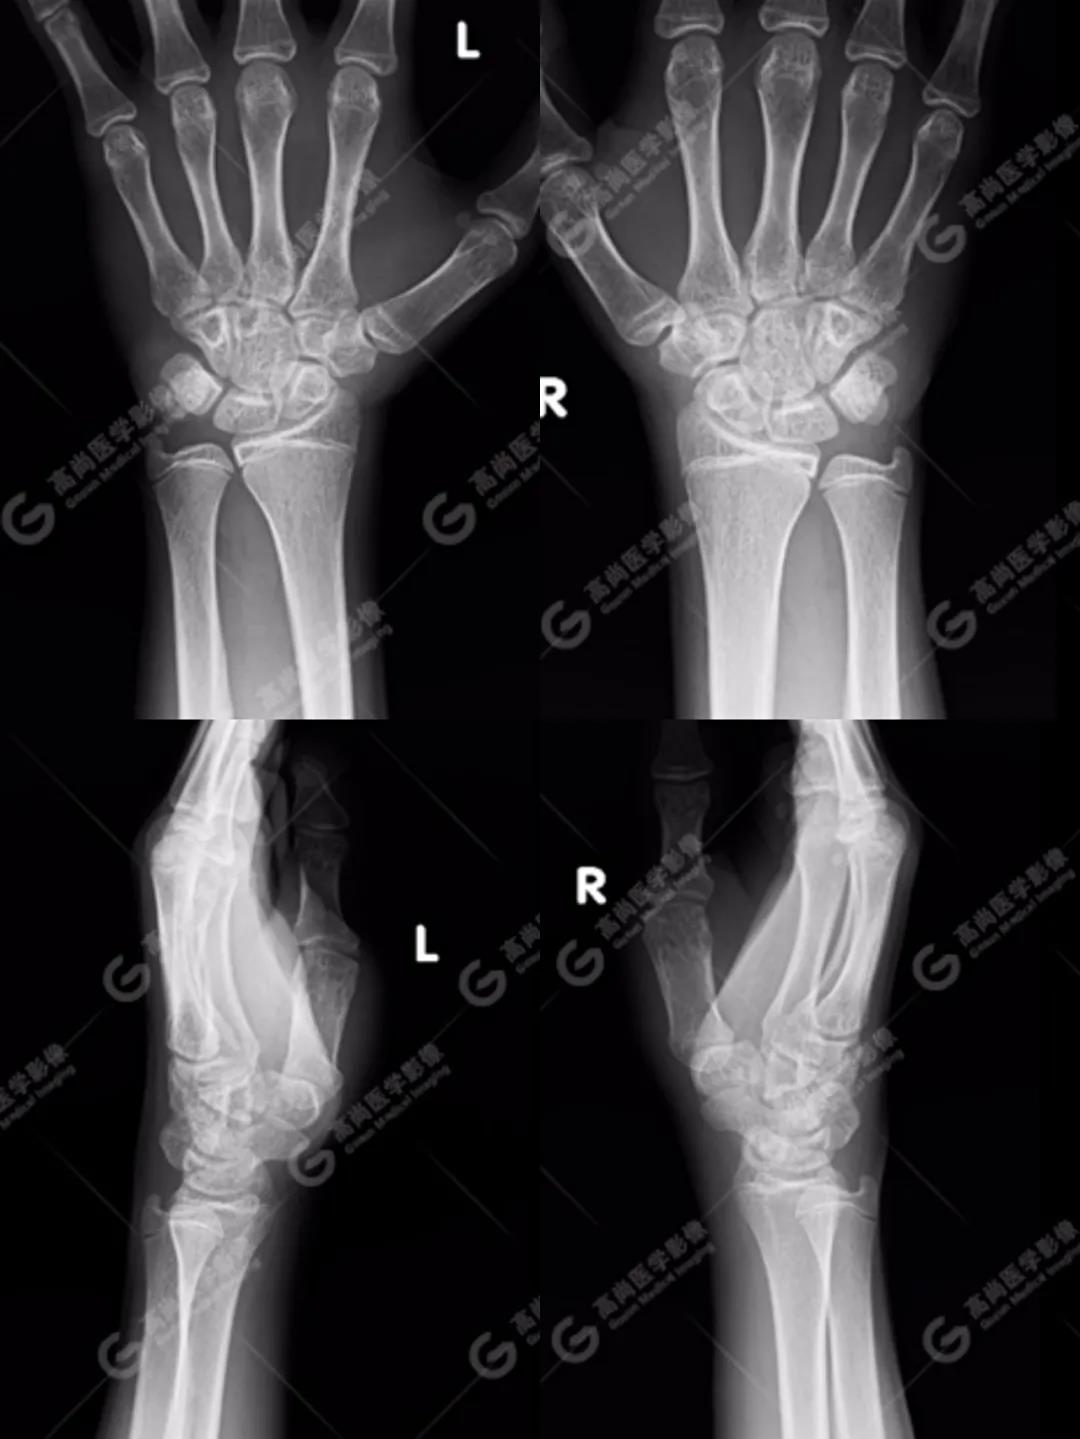

1、雙腕關(guān)節(jié)正側(cè)位平片

按照臨床診療的常規(guī)思路,遇到這種情況首先行X線平片攝影檢查(老百姓通俗講的“照片”)。

如下圖所見:雙腕關(guān)節(jié)諸骨未見明顯骨折征象。

沒有看到明顯的骨折線,患者的疼痛是不是軟組織損傷造成的、回家擦一些紅花油之類的外用藥就ok了的“小問題”呢?考慮到孩子即將面臨考試,家長(zhǎng)還是不放心,擔(dān)心X線影像重疊等因素造成漏診,想進(jìn)一步明確,提出進(jìn)行CT檢查(由于成像原理的差別,CT對(duì)于細(xì)微骨折的顯示要明顯優(yōu)于常規(guī)X線攝影)。